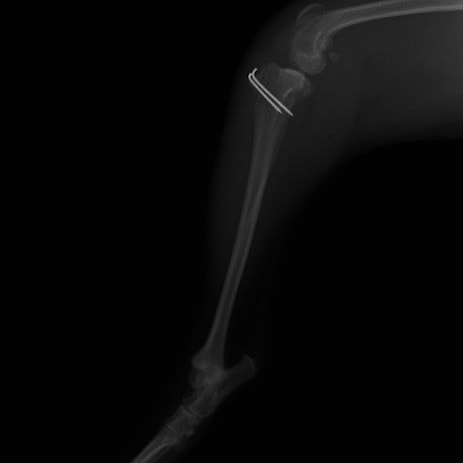

■ 症例22 ポメラニアン 1歳5か月 去勢雄

左後肢の挙上を主訴に来院した。整形学的検査、レントゲン検査より左右の膝蓋骨脱臼(左GradeⅡ〜Ⅲ、右Grade Ⅱ)を認めた。また、脛骨の前方引き出し試験の際に、引き出し兆候は認められないものの、疼痛が認められたため、前十字靭帯の損傷が疑われた。術中における、目視および関節内の操作によって、前十字靭帯の損傷や過伸展といった異常が認められなかったため、膝蓋骨脱臼の整復のみ実施した。手術手技は縫工筋及び内側広筋の解放、脛骨粗面の外側転位、滑車ブロック形造溝術、内外側関節包の縫縮を実施した。本症例は跛行もなく経過良好である。しかし、頸骨高平部の角度(TPA)が 右26.2°、左24.9°であり、解剖学的に前十字靭帯損傷のリスクが高いことから今後の経過に注意が必要である。